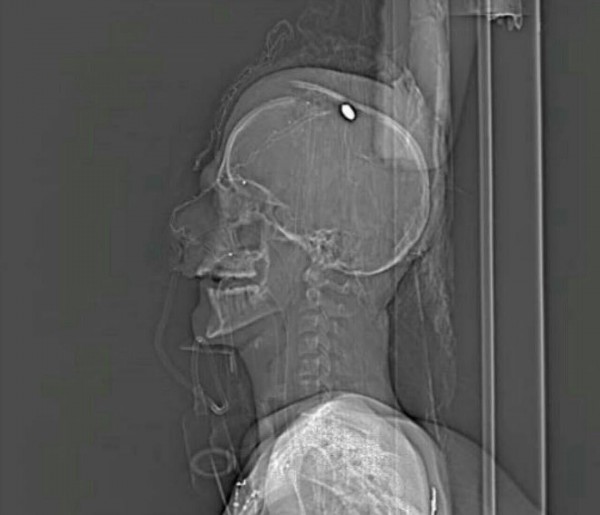

أنفاس الشاب الواقف على أعتاب الحياة والموت، صوت الأجهزة والأوكسجين، العين المتورمة البنفسجية، الشفاه المنتفخة، وجرح بين العينين، ورصاصة في عمق الرأس، هذا الشاب ذو السبعة عشر ربيعاً، ترجف مع أنفاسه آلاف القلوب، فالخوف عليه كبير، والموت يلوح كبوابة خلاص أمام شاب يتيم معذب مظلوم من قبل نظام يرتبط منذ نشأته ببلد يتميز بقدرته على قتل أحلام البشر والشعوب في الحرية والاستقلال، منذ إن كان امبراطورية، بلد لم يترك البلاد التي استعمرها، بل عاد إليها أقوى وأشرس وأكثر قسوة.

شهور من المرابطة أمام منزل آية الله قاسم دون راحة، انتهت بطلقة رصاص في الرأس، أشهرٌ من النوم خارج المنزل، أشهر من القلق، أشهر من الصبر الطويل المرّ، رصاصة غادرة عجز الأطباء عن إخراجها، رصاصة من يد جبان رعديد يغطي وجهه، رصاصة من فداوي بن فداوية أطلقها وهرب ككلب مذعور، جبان يعمل مع جهة جبانة لم تعلن حتى الآن أنها قامت بالهجوم. لماذا؟ لأنها، لم تعد مضطرةً للكذب.

سلطة أرسلت بالدم جوابها على أية وساطة تلوح في الأفق، لكنه ليس دمها، بل دمنا، دم مصطفى أحمد حمدان، الشاب المرابط الذي تتمتم له الشفاه بالدعاء، وتدق القلوب مرتعشة خوفاً عليه.